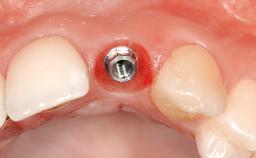

Mauricio Araujo and Flauvia Matarazzo present this straightforward clinical case, demonstrating the potential effect of implant placement depth on the resolution of peri-implant treatment. A 42-year-old systemically healthy female patient, a non-smoker with no history of periodontitis, was treated at the Dental Clinic at the State University of Maringá, Brazil between 2008 and 2009, when she received five implants restored with single crowns at sites 14, 26, 27, 36, and 46. After delivery of the implant-supported prosthetic restorations, the patient was enrolled in the supportive peri-implant therapy (SPiT) maintenance program at the same university.